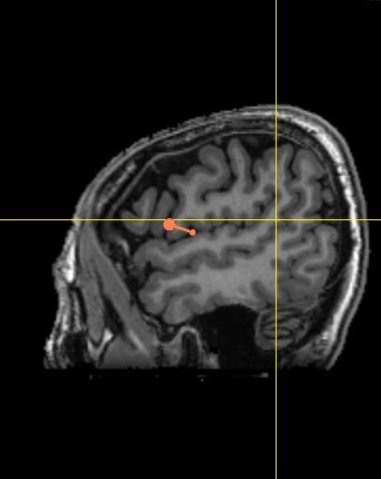

應用3D技術定位右側前額下迴(圖中橘色的指示記號)(長庚醫院提供)